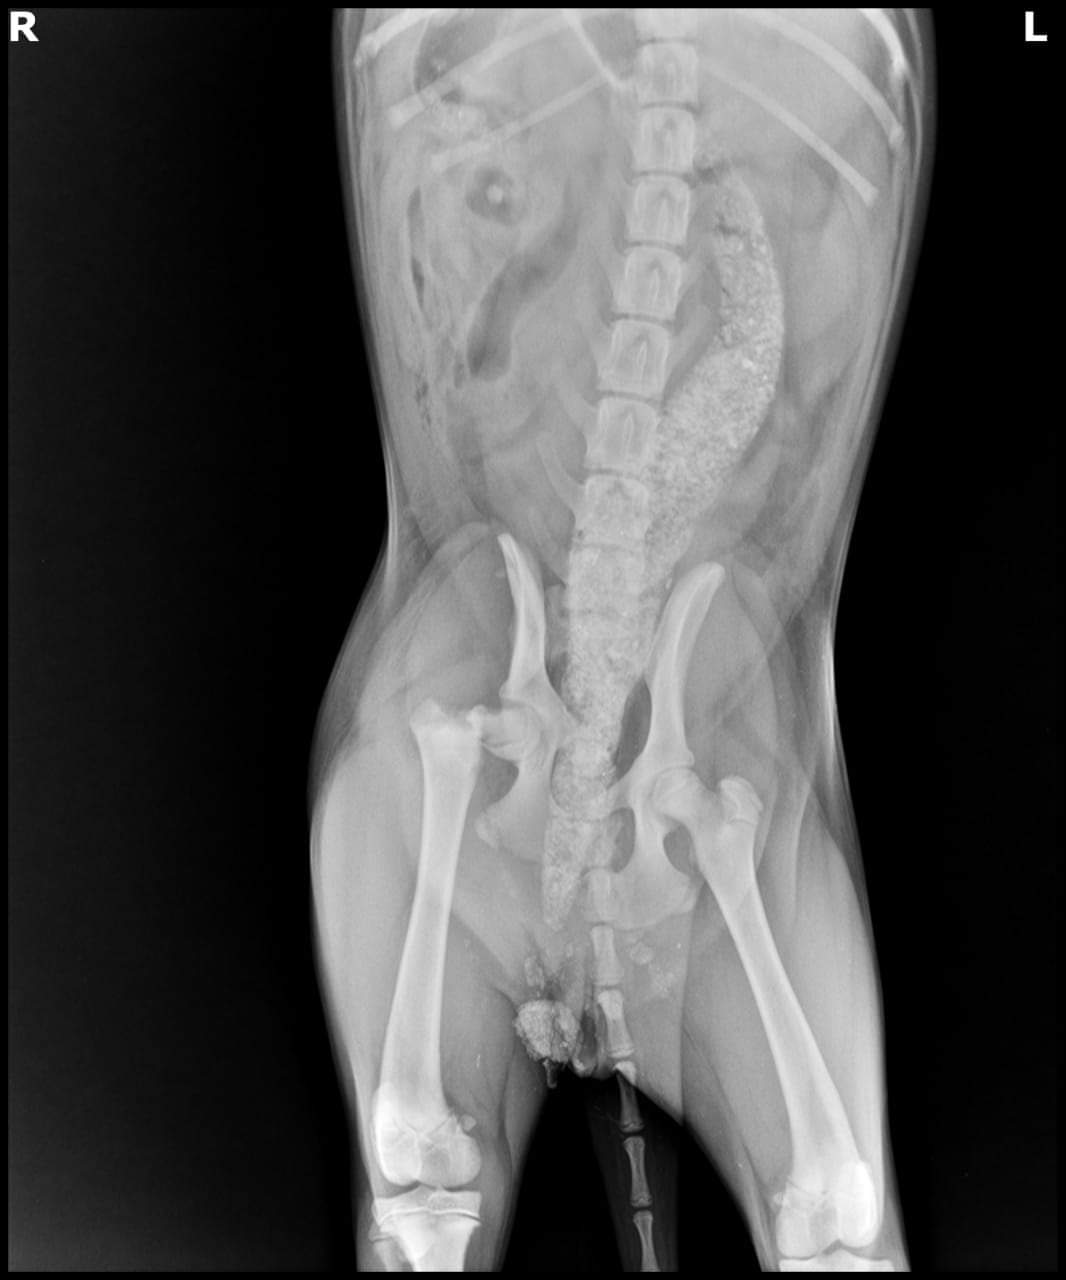

وأضافت لـ القاهرة 24: بتوقيع الكشف الطبي عليه وإجراء الأشعة اللازمة، تبين أنه مصاب بكسر في الحوض وعظمة الفخذ، ليحتاج إلى إجراء عمليتين جراحتين.